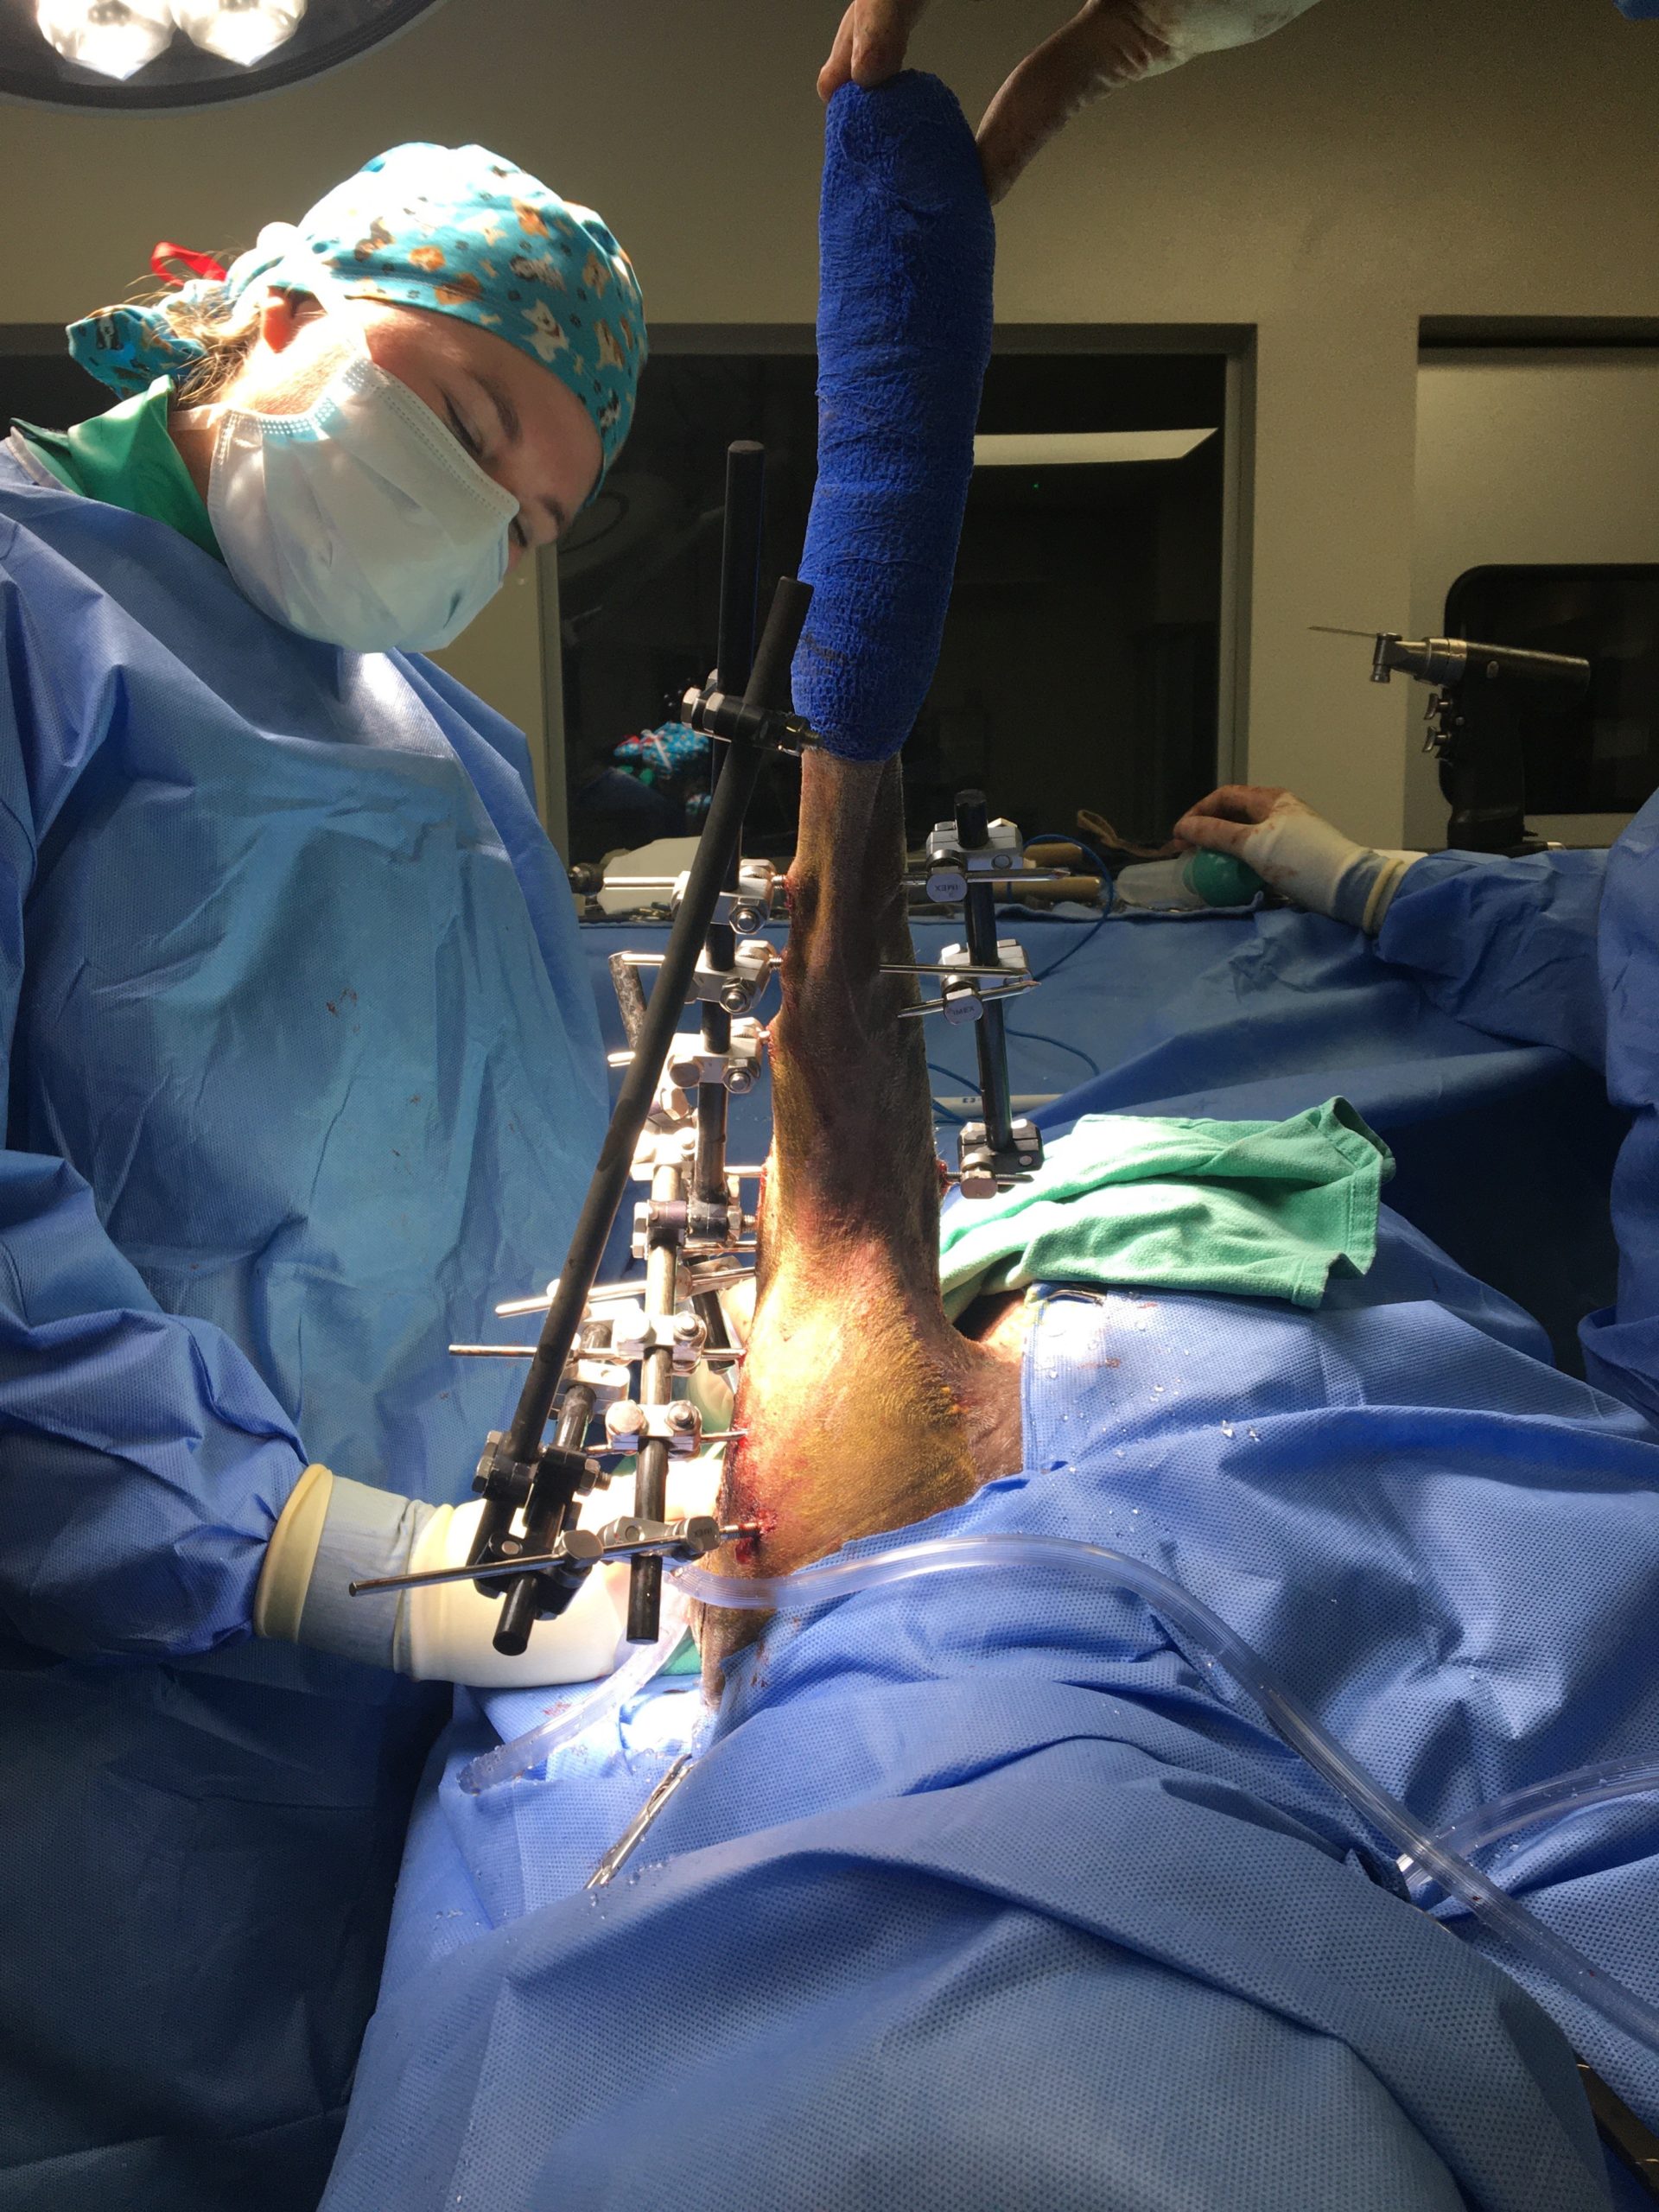

Figure 5: Intra-operative after fracture fixation with external fixator